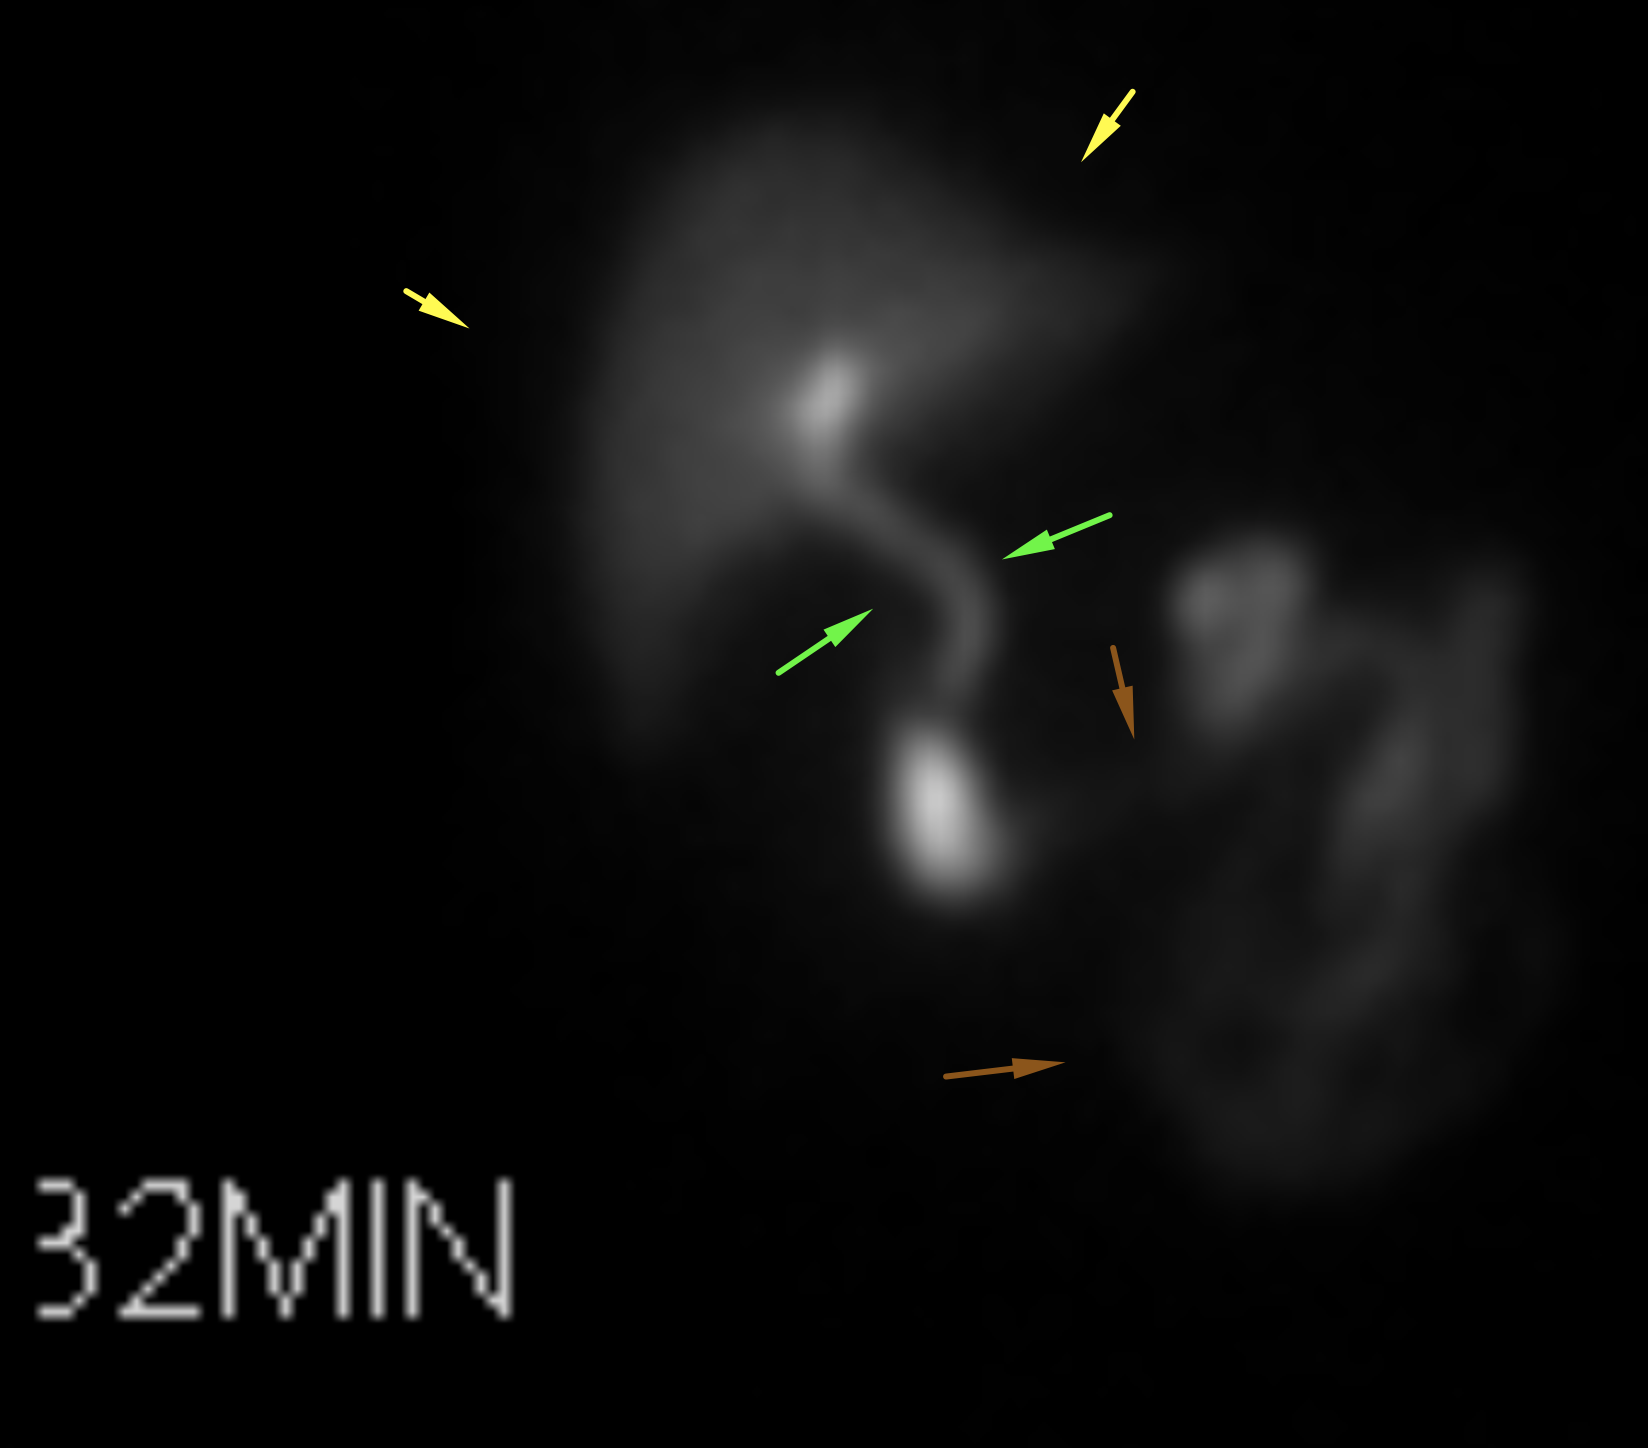

Age: 84

Sex: Male

Indication: Left-sided chest pain, recent cholecystectomy

Radiotracer: Tc99m mebrofenin (an iminodiacetic acid analog)

Sample ReportPositive for biliary leak, which is drained by the existing surgical drains.

No evidence of intra-abdominal bile collections.

No evidence of common bile duct obstruction.